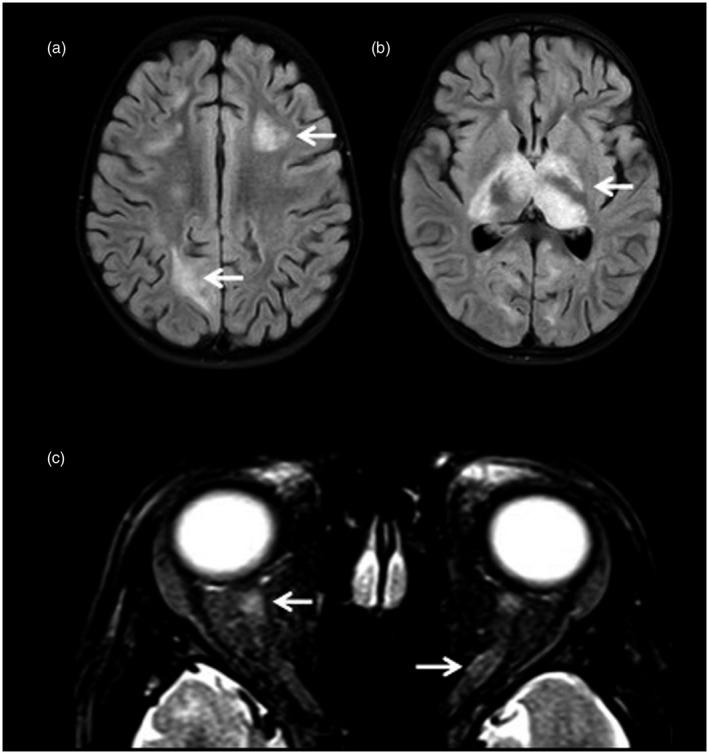

MOGAD-MRI 和 OCT 的临床和神经影像学表现。

Clinical and neuroimaging findings in MOGAD-MRI and OCT.

Myelin oligodendrocyte glycoprotein antibody-associated disorders (MOGAD) are rare in both children and adults, and have been recently suggested to be an autoimmune neuroinflammatory group of disorders that are different from aquaporin-4 autoantibody-associated neuromyelitis optica spectrum disorder and from classic multiple sclerosis. In-vivo imaging of the MOGAD patient central nervous system has shown some distinguishing features when evaluating magnetic resonance imaging of the brain, spinal cord and optic nerves, as well as retinal imaging using optical coherence tomography. In this review, we discuss key clinical and neuroimaging characteristics of paediatric and adult MOGAD. We describe how these imaging techniques may be used to study this group of disorders and discuss how image analysis methods have led to recent insights for consideration in future studies.

髓鞘少突胶质细胞糖蛋白抗体相关疾病(MOGAD)在儿童和成人中均较为罕见,最近有研究提示其为一种不同于水通道蛋白 4 自身抗体相关视神经脊髓炎谱系疾病和经典多发性硬化的自身免疫性神经炎症性疾病组。MOGAD 患者中枢神经系统的体内影像学检查在评估脑、脊髓和视神经磁共振成像以及使用光学相干断层扫描进行视网膜成像时显示出一些独特特征。在这篇综述中,我们讨论了儿科和成人 MOGAD 的关键临床和神经影像学特征。我们描述了这些影像学技术如何用于研究这组疾病,并讨论了图像分析方法如何为未来研究提供新的思路。